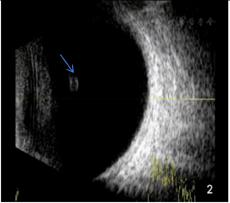

免疫球蛋白A 5.73 g/L,免疫球蛋白M 0.42 g/L,补体C3 0.664 g/L,抗nRNP抗体阳性(+++),抗核小体抗体阳性(++),抗核糖体P蛋白抗体阳性(+++),抗核糖体-核型1核均质型(AC-1),抗组蛋白抗体阳性(++),核型1滴度阳性1:1280,白细胞计数1.74×109/L,红细胞沉降率:30 mm/h,尿蛋白:+。眼科检查:视力右:1.0,左:0.8,眼压右:15 mmHg(1 mmHg=0.133 kPa),左:14 mmHg,双眼睑未见明显异常,睑球结膜无充血,角膜透明,前房深度适中,房水清,虹膜纹理清,瞳孔圆,直径约3 mm,对光反射灵敏,晶状体周边可见散在白色小片状混浊,右眼下方玻璃体腔内可观察到一半透明圆形悬浮物,表面上可见少量色素附着,且囊壁光滑,并随眼球运动,散瞳后右眼眼底可见视盘界清,色红润,血管走形正常,A:V=2:3,视网膜平伏,黄斑区中心凹反光可见(图1A),左眼眼底可见视盘界清,色红润,颞上方血管弓静脉走形稍迂曲,视网膜平伏,黄斑区中心凹反光可见(图1B)。眼部B超示:右眼可见一环形中高回声(图2)。超声活体显微镜(UBM)示:双眼睫状体6点位各见一囊肿,囊肿呈圆形,囊内为无回声区,外周回声与睫状体回声强度基本相同的回声(图3A、图3B)。眼前节照相示:右眼玻璃体腔内有半透明圆团状囊样悬浮物,其表面有棕黄色色素沉着(图4)。初步诊断为:右眼玻璃体囊肿、双眼睫状体囊肿、双眼先天性白内障、系统性红斑狼疮。

诊断依据:患者,女性,25岁,因反复发热、四肢多关节疼痛伴皮疹40 d,患者自觉右眼眼前有明显的漂浮物,眼科检查:视力右:1.0,左:0.8,眼压右:15 mmHg,左:14 mmHg,晶状体周边可见散在白色小片状混浊,右眼下方玻璃体腔内可观察到一半透明圆形悬浮物,表面上可见少量色素附着,且囊壁光滑,并随眼球运动,眼部B超示:右眼可见一环形中高回声。超声活体显微镜(UBM)示:双眼睫状体6点位各见一囊肿,囊肿呈圆形,囊内为无回声区,外周回声与睫状体回声强度基本相同的回声。眼前节照相示:右眼玻璃体腔内有半透明圆团状囊样悬浮物,其表面有棕黄色色素沉着,结合患者眼部B超、超声活体显微镜、眼前节照相表现可诊断为玻璃体囊肿及睫状体囊肿。